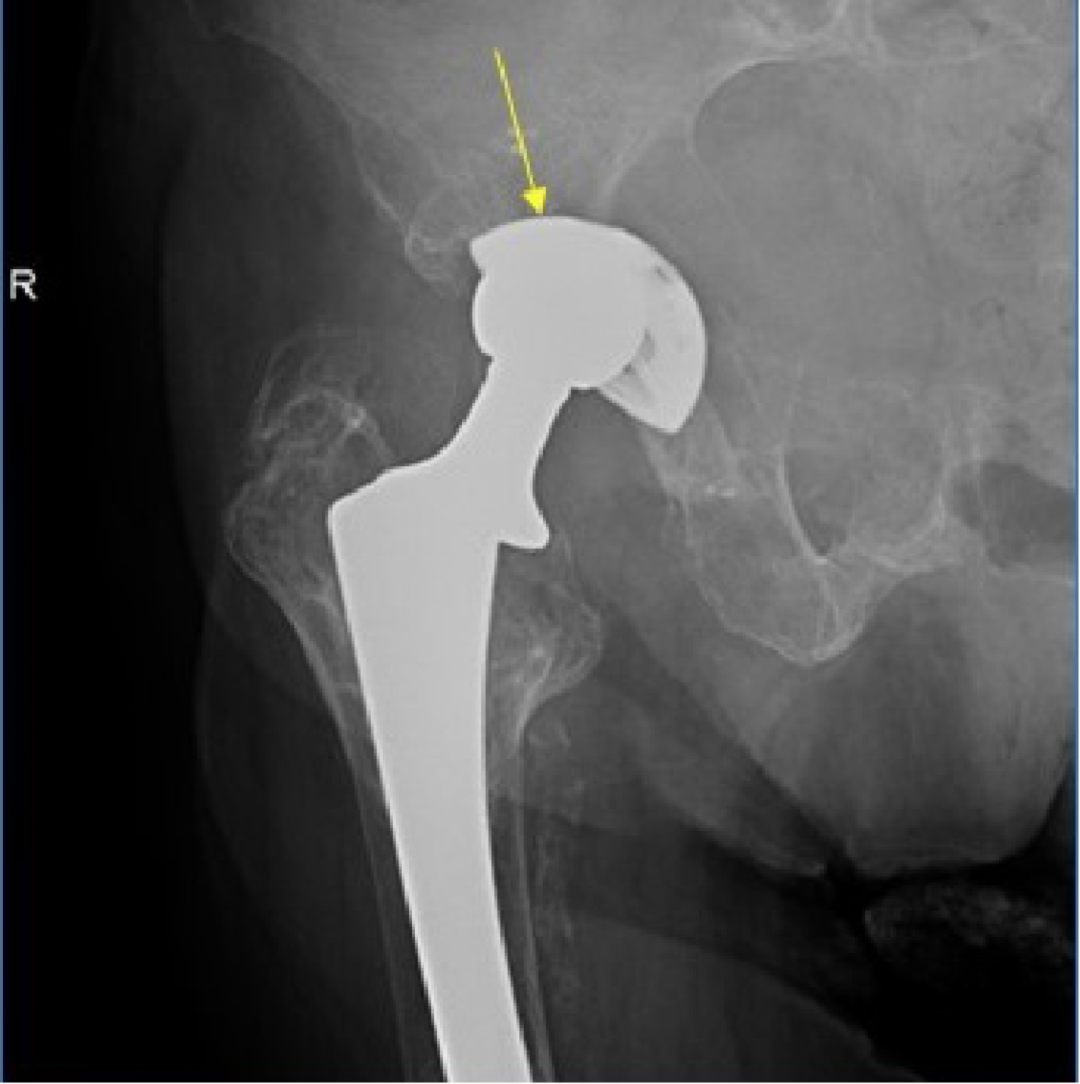

5. Metal-on-metal(MOM)disease:

假性滑囊,是金属对金属髋关节置换的组织反应;表现为髋关节假体周围的滑囊。最常见的部位是:髋臼上缘、大粗隆和小粗隆。

人工髋关节置换术。假体周围囊性肿块(箭头)